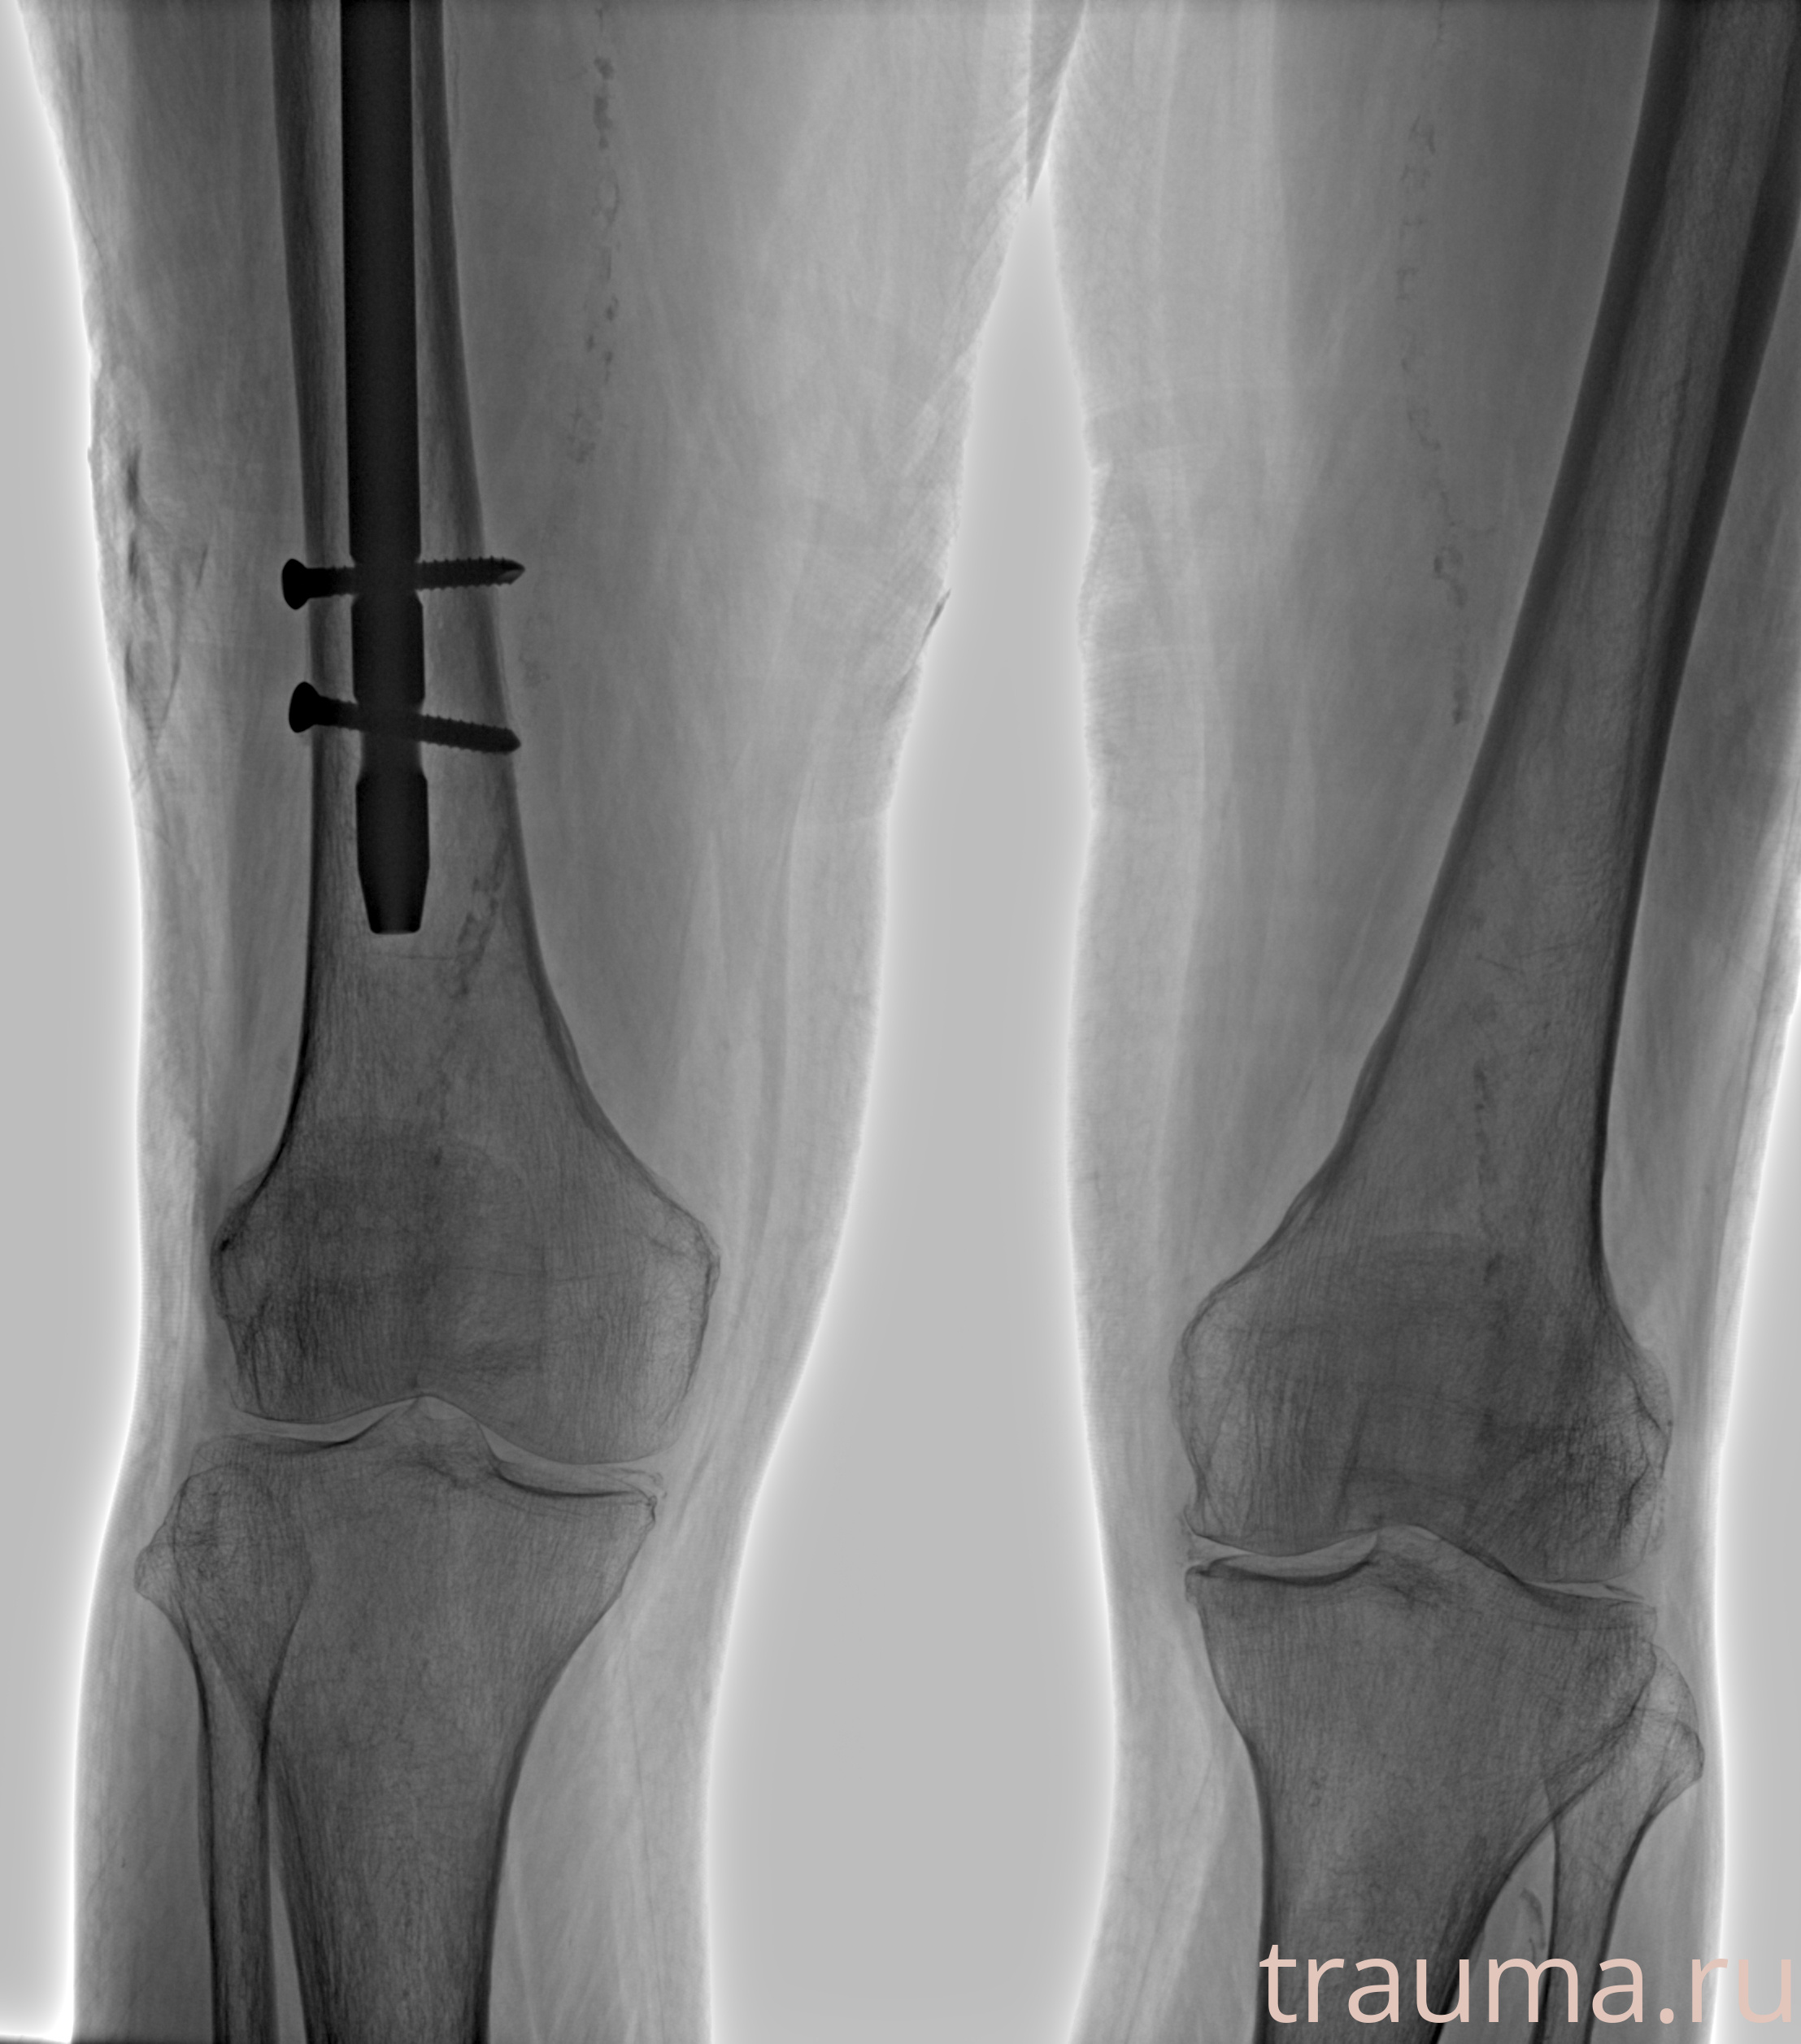

Рентгенограммы

Рентген на дому: по вашему адресу приезжает врач-рентгенолог, травматолог-ортопед с мобильным рентгеновским аппаратом, проводит диагностику травмы или заболевания, делает необходимые рентгенограммы, дает рекомендации по дальнейшему лечению. Получить качественные снимки в домашних условиях возможно благодаря уникальной методике, разработанной МосРентген Центром для института  Склифосовского